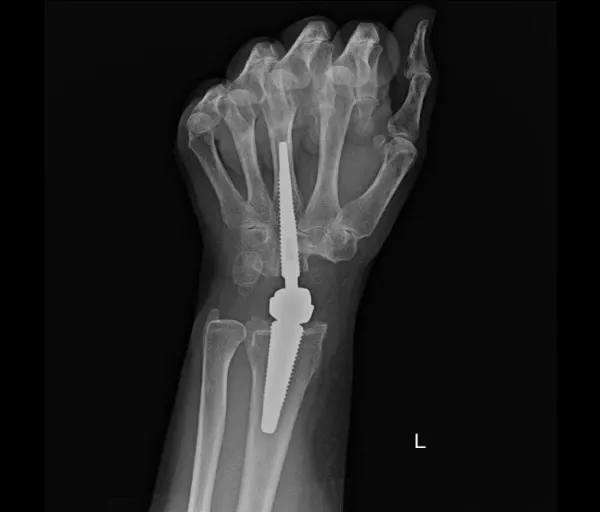

- Scaphoidectomie + four-corner fusieHet scaphoid wordt verwijderd, vier polsbeentjes worden vastgezetOngeveer 45% beweeglijkheid en 80% kracht blijft behouden

- Proximale rij carpectomieVerwijderen van scaphoid, lunatum en triquetrumNieuwe scharnierfunctie tussen capitatum en onderarmResultaten vergelijkbaar met four-corner fusieSoms aangevuld met een resurfacing-prothese

- Totale polsartrodeseHele pols wordt vastgezetVingers kunnen wel nog bewegenGeschikt voor zwaar belastend werk

- PolsprotheseVervanging van het polsgewrichtBewegingsbeperking blijft, maar voldoende voor dagelijkse activiteitenBelasting moet beperkt blijven om vroegtijdige slijtage te voorkomen

- DRUJ-protheseVervanging van alleen het draai-gewricht tussen spaakbeen en ellepijp